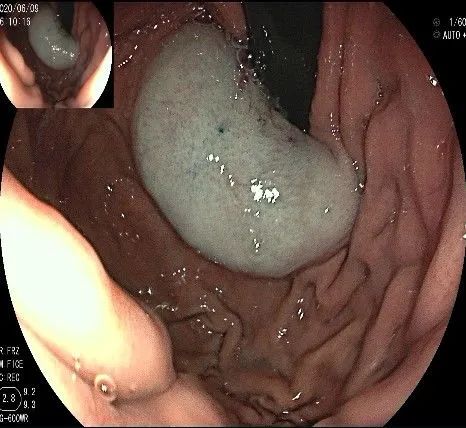

再次进镜观察,齿状线炎性息肉的地方,用圈套器圈套后通电切除。

瘤子切除后,在粘膜切开的地方,固有肌层的纵形肌处形成一个开口。

倒镜观察,隆起已经消失。

夹闭创面的时候做胃镜吸引,利于创面闭合。

创面夹闭完成,反复冲洗观察,无出血及穿孔。结束手术,等待病理结果。